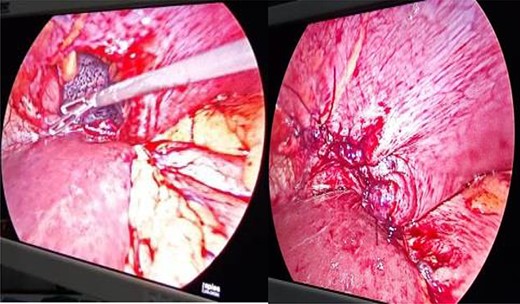

Patients were placed in right lateral position with head end slightly elevated (20–30°). The defects were identified, contents (if any) were reduced and the defects were closed with polypropylene suture (Fig. 4).

Defect in left hemidiaphragm with visible collapsed lung and closure of defect.